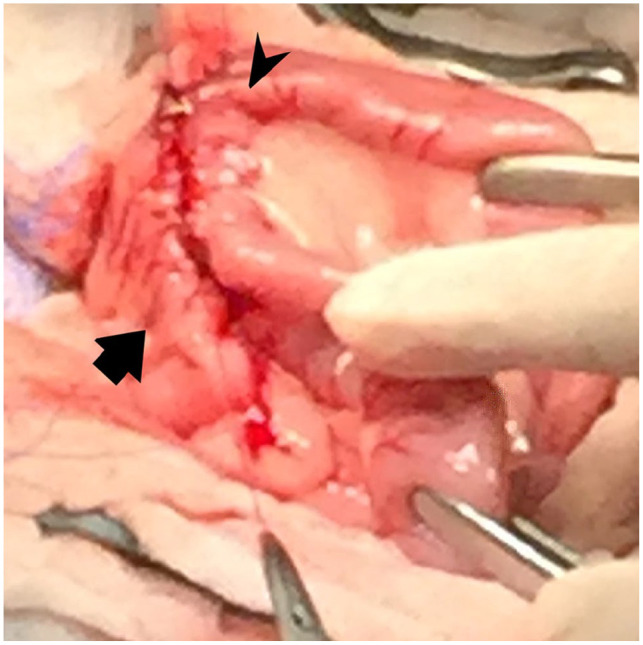

Case summary: A 2-year-old female spayed domestic shorthair cat was presented for evaluation of severe thickening of the proximal duodenum identified on abdominal ultrasound after a 1-year history of vomiting. At surgery, a proximal duodenal mass encompassed the areas of the major and minor duodenal papillae. A gastrojejunostomy was performed to bypass the proximal duodenum and maintain the integrity of the major duodenal papilla. Histopathology revealed changes consistent with feline eosinophilic sclerosing fibroplasia. The cat was treated with prednisolone and survived for 2.5 years. It was euthanized for bronchopneumonia.

Relevance and novel information: This case report describes a surgical approach for cats with lesions involving the pylorus and proximal duodenum. Gastrojejunostomy provided a therapeutic option that preserved exocrine pancreatic and biliary secretion in this cat.